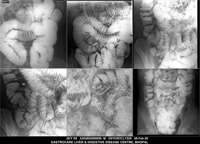

Section: ENTEROCLYSIS

Total: 205 Cases